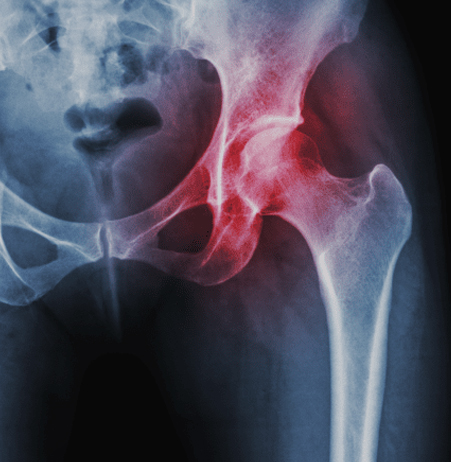

Cirugías de Cadera

Reemplazo de cadera

Imágenes diagnósticas con rayos X en Guatemala